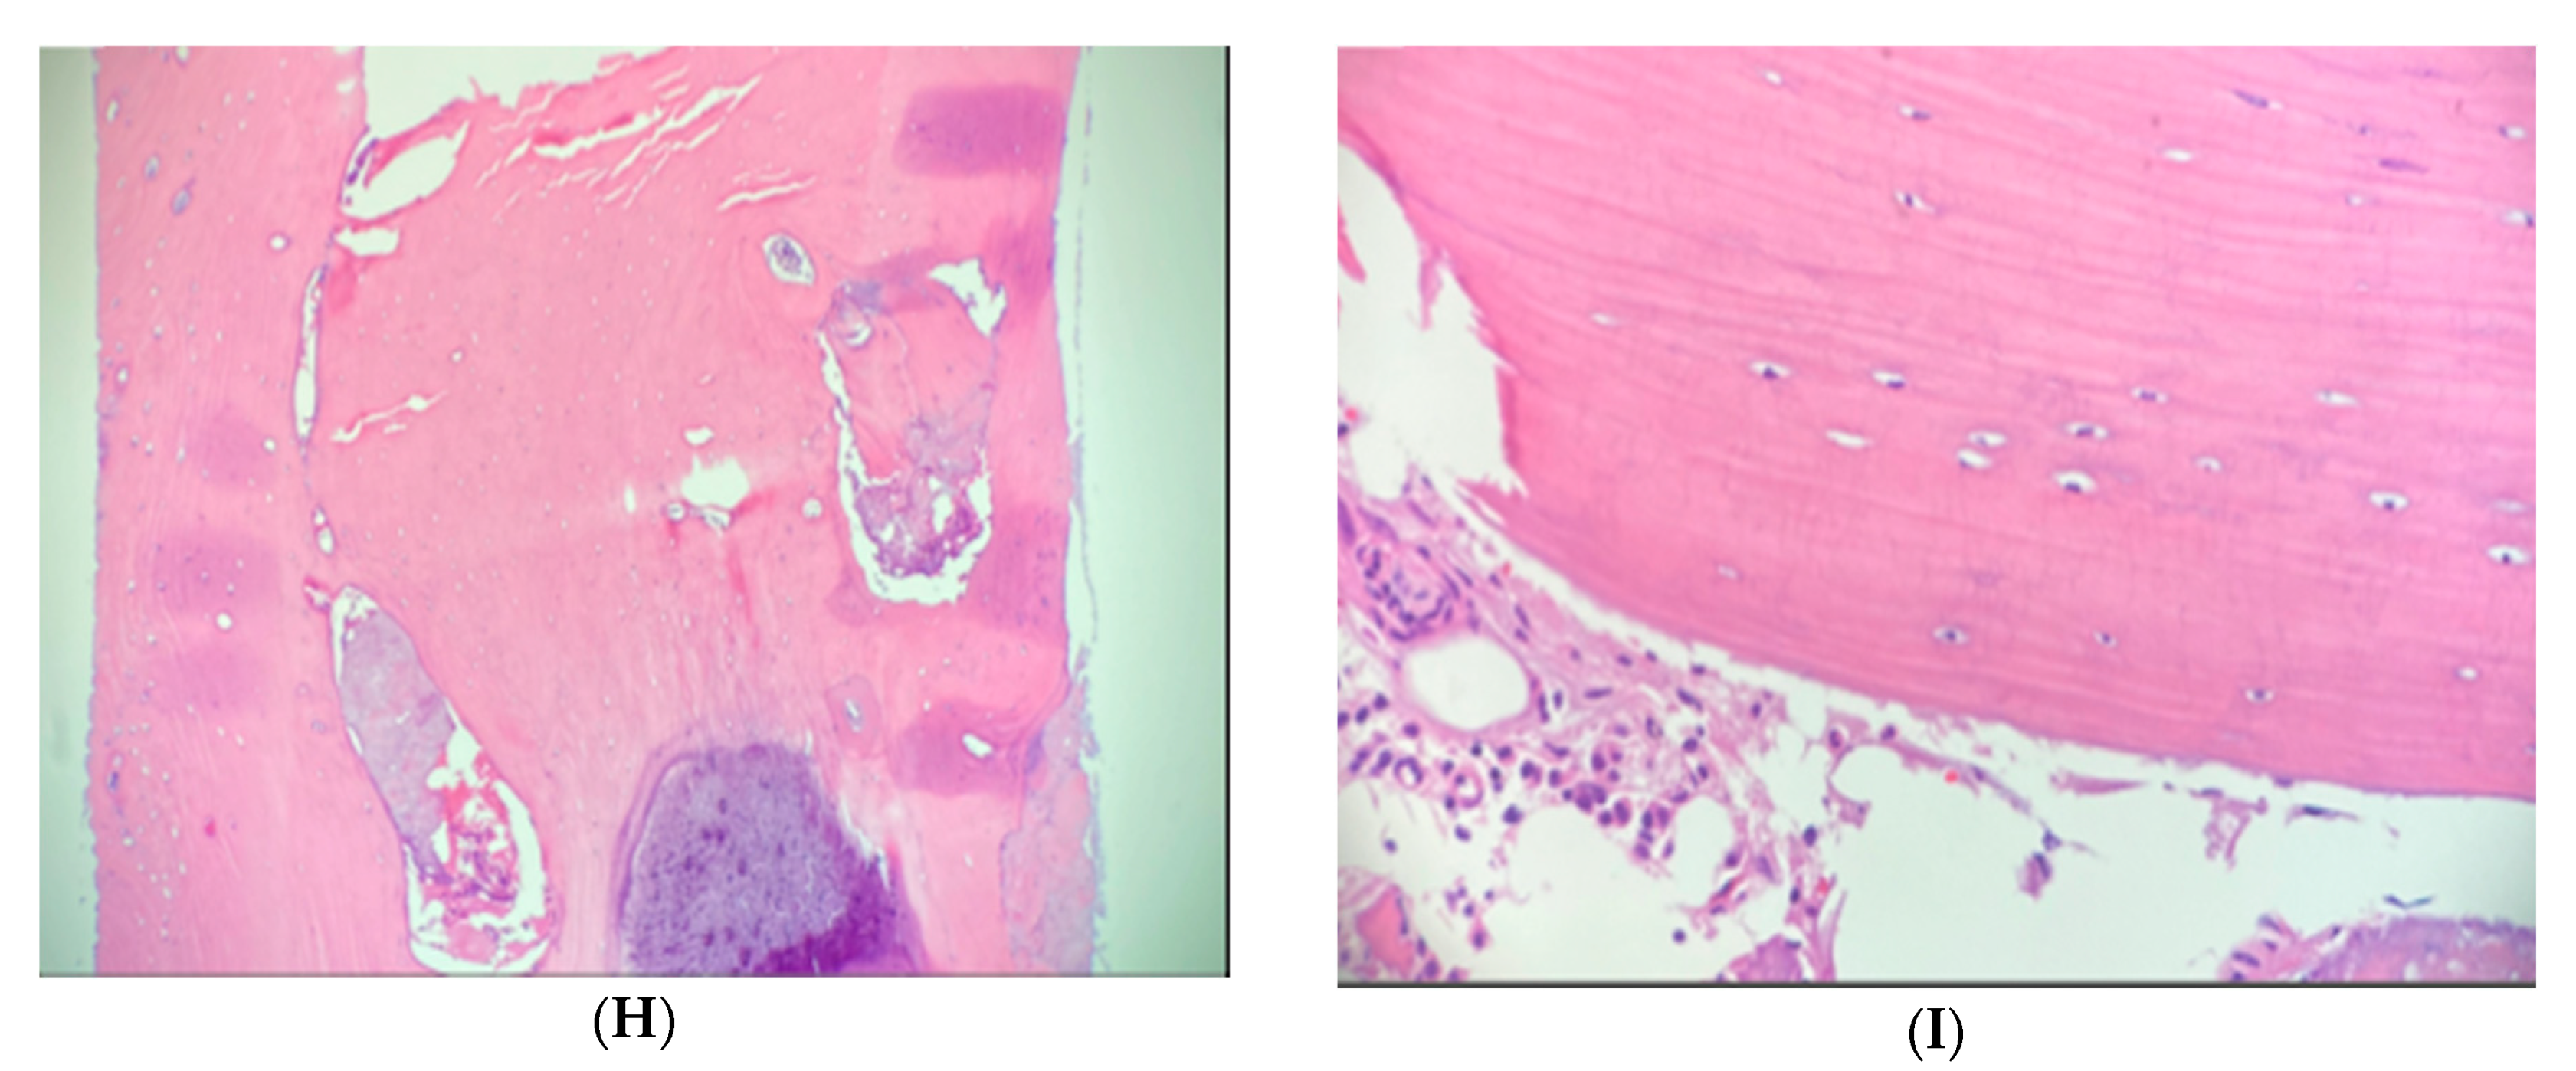

Figure 4. (AI) Case 2. Pelvic axial CT shows enlargement, atypical central radiolucency and osteoid osteoma mimicking BI in a patient with osteopoikilosis. (AC) Initial CT shows a right sacral lesion (white arrow) measuring 8 mm, left anterior iliac centrally radiolucent less sclerotic lesion (black arrow) and sclerotic bone lesion in the left posterior ilium (red arrow) near the SI joint. (D,E) Repeat CT 5-years later shows enlargement to 18 mm in right sacrum (white arrow), stable centrally radiolucent left anterior iliac lesion (black arrow) and left posterior iliac lesion (red arrow) correlating with the patient’s pain, TTP (tenderness to palpation) and increased BS (bone scan) uptake. (F) NM whole body bone scintigraphy demonstrating increased uptake in the left posterior ilium adjacent to the SI joint. (G) Higher magnification emphasizes increased uptake. Given the atypical features, biopsies of the right sacrum (due to enlargement and increased activity on BS) and left posterior ilium (due to pain and local tenderness) were performed. These established the diagnoses of atypical bone island and osteoid osteoma (OO), respectively. Radiofrequency ablation of the OO resolved her symptoms. Left anterior iliac lesion was diagnosed clinically as BI. (H,I) Case 2. Hematoxylin and eosin (H&E) stain of right sacral bone biopsy, establishing a diagnosis of atypical bone island. (H) Magnification 10× (low power view) of the core biopsy showing cortical type bone. (I) Magnification 40× (high power view) of the specimen, displaying lamellar bone with small osteocytes and normal marrow components.